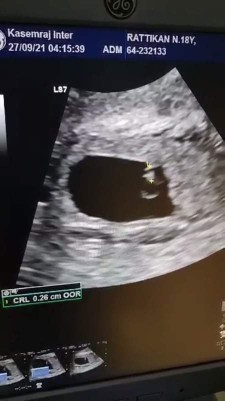

อายุครรภ์ 5 week กว่า แต่ยังไม่เห็นตัวอ่อน

แบบนี้คือปกติไหมค่ะ กลัวท้องลม

รอตอน 8-12 weeks ค่อยไป u/s อีกรอบนะคะ ตอนนี้ยังท้องอ่อนๆ อาจจะยังไม่เห็นตัวอ่อนค่ะ จะเจอได้แต่ถุงหุ้มตัวอ่อนค่ะ